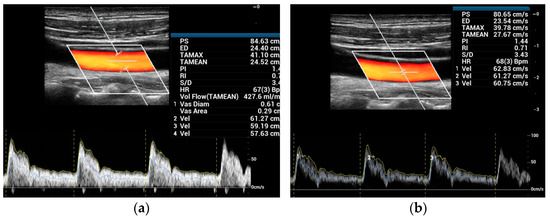

:1. Introduction

2.1. V Flow Technique Description

2.2. Ultrasound Scan Setup